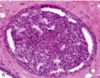

What is this showing?

Atypical ductal hyperplasia- is recognized by its histologic resemblance to ductal carcinoma in situ (DCIS). It consists of a relatively monomorphic proliferation of regularly spaced cells (with no overlap), sometimes with cribriform spaces.

Most surgeons will remove cells with atypical ductal hyperplasia